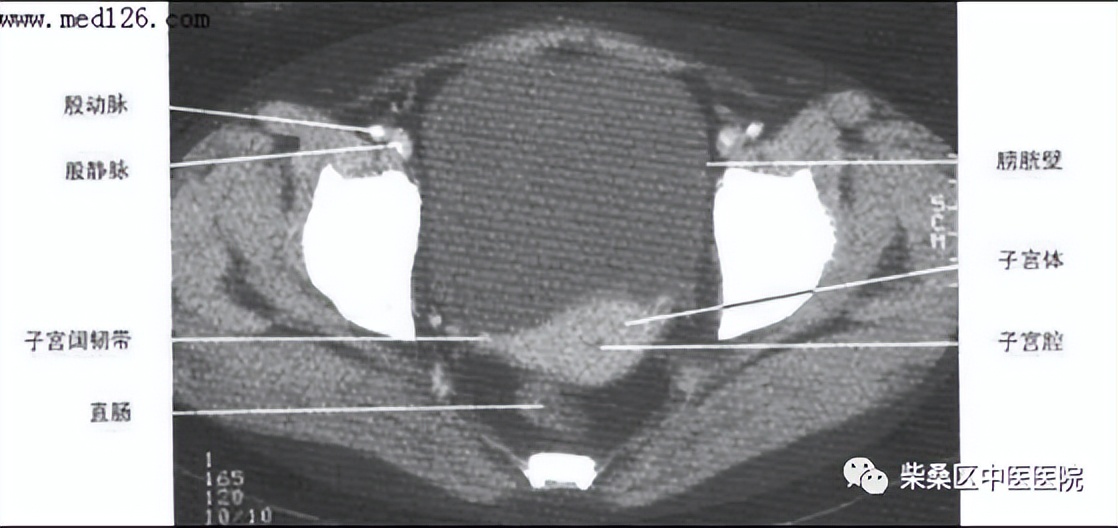

女性盆腔CT解剖结构

正常膀胱充盈可见水样密度影,还可以看见膀胱壁薄厚,正常充盈时,膀胱壁约5mm。例如膀胱有肿瘤、结石以及膀胱憩室等疾病时都需要在膀胱充盈状态时才会显示。另外在女性盆腔CT的检查中,充盈饱满的膀胱可以与子宫附件囊肿进行有效区分。